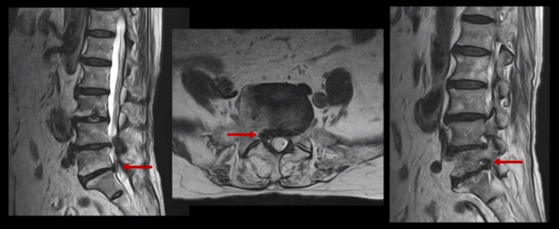

이분의 허리 MRI를 보면 여러 마디에 퇴행성 변화가 있습니다.

우선 5번 1번 마디를 보면 오른쪽으로 디스크도 밀려나와있고 또한 추간공도 좁아져 있는 것이 보입니다. 이걸 협착이라고 합니다.

1년 전부터의 오른쪽 다리 증상은 이 추간공이 좁아져서 생긴 추간공협착증 증상 때문인 것으로 보입니다.

또 위로 올라가서 2번 3번 관절을 보면 왼쪽으로 디스크가 파열되어 위로 밀려 올라가있고

3번 4번 마디를 보면 왼쪽으로 디스크가 많이 밀려나와 있습니다.

이 두 마디가 왼쪽 증상, 특히 허벅지 통증을 일으키는 원인으로 보입니다. 이렇게 여러 마디가 안 좋을수록, 또 고령일수록 수술하기가 더 까다로워지는데 또 큰 문제는 이 환자분은 근감소증이 심하게 진행된 상태로, 여기 MRI에서 보시다시피 허리 하부의 기립근 근육이 전부 지방으로 변해버려 근육 자체가 거의 없는 상태인 것입니다.

그런데 한편으로 다행인 것은 이분 척추는 여러 마디 다 문제이기는 하지만 저희가 보는 환자 중에서 신경 구멍이 아예 보이지 않을 정도로 막힌 협착증 환자분이나 신경 구멍을 거의 다 막을 정도로 심하게 디스크가 파열된 환자분들에 비해서는 신경의 눌림 정도는 많이 심하시지는 않은 상태셨습니다. 이런 상태라면 더 빠른 호전을 기대해볼 수 있을까요?